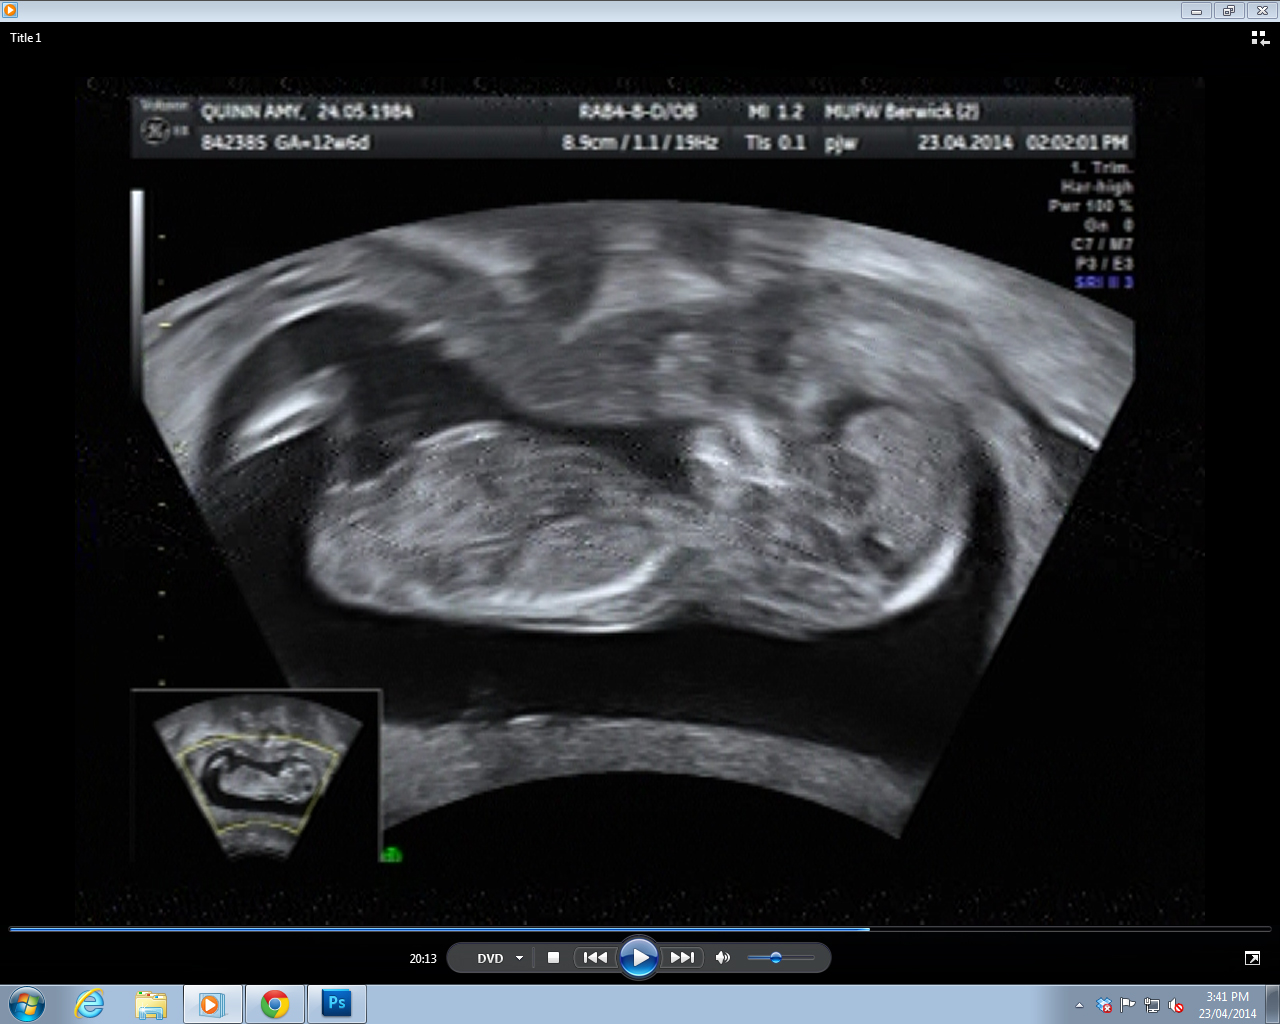

Three nub shots I was able to get, pulled off the DVD. I really didn't have much to work with - in 30 minutes of footage, these were the ONLY clear(ish) nub shots the whole time.

Attachment 18363Attachment 18364Attachment 18365